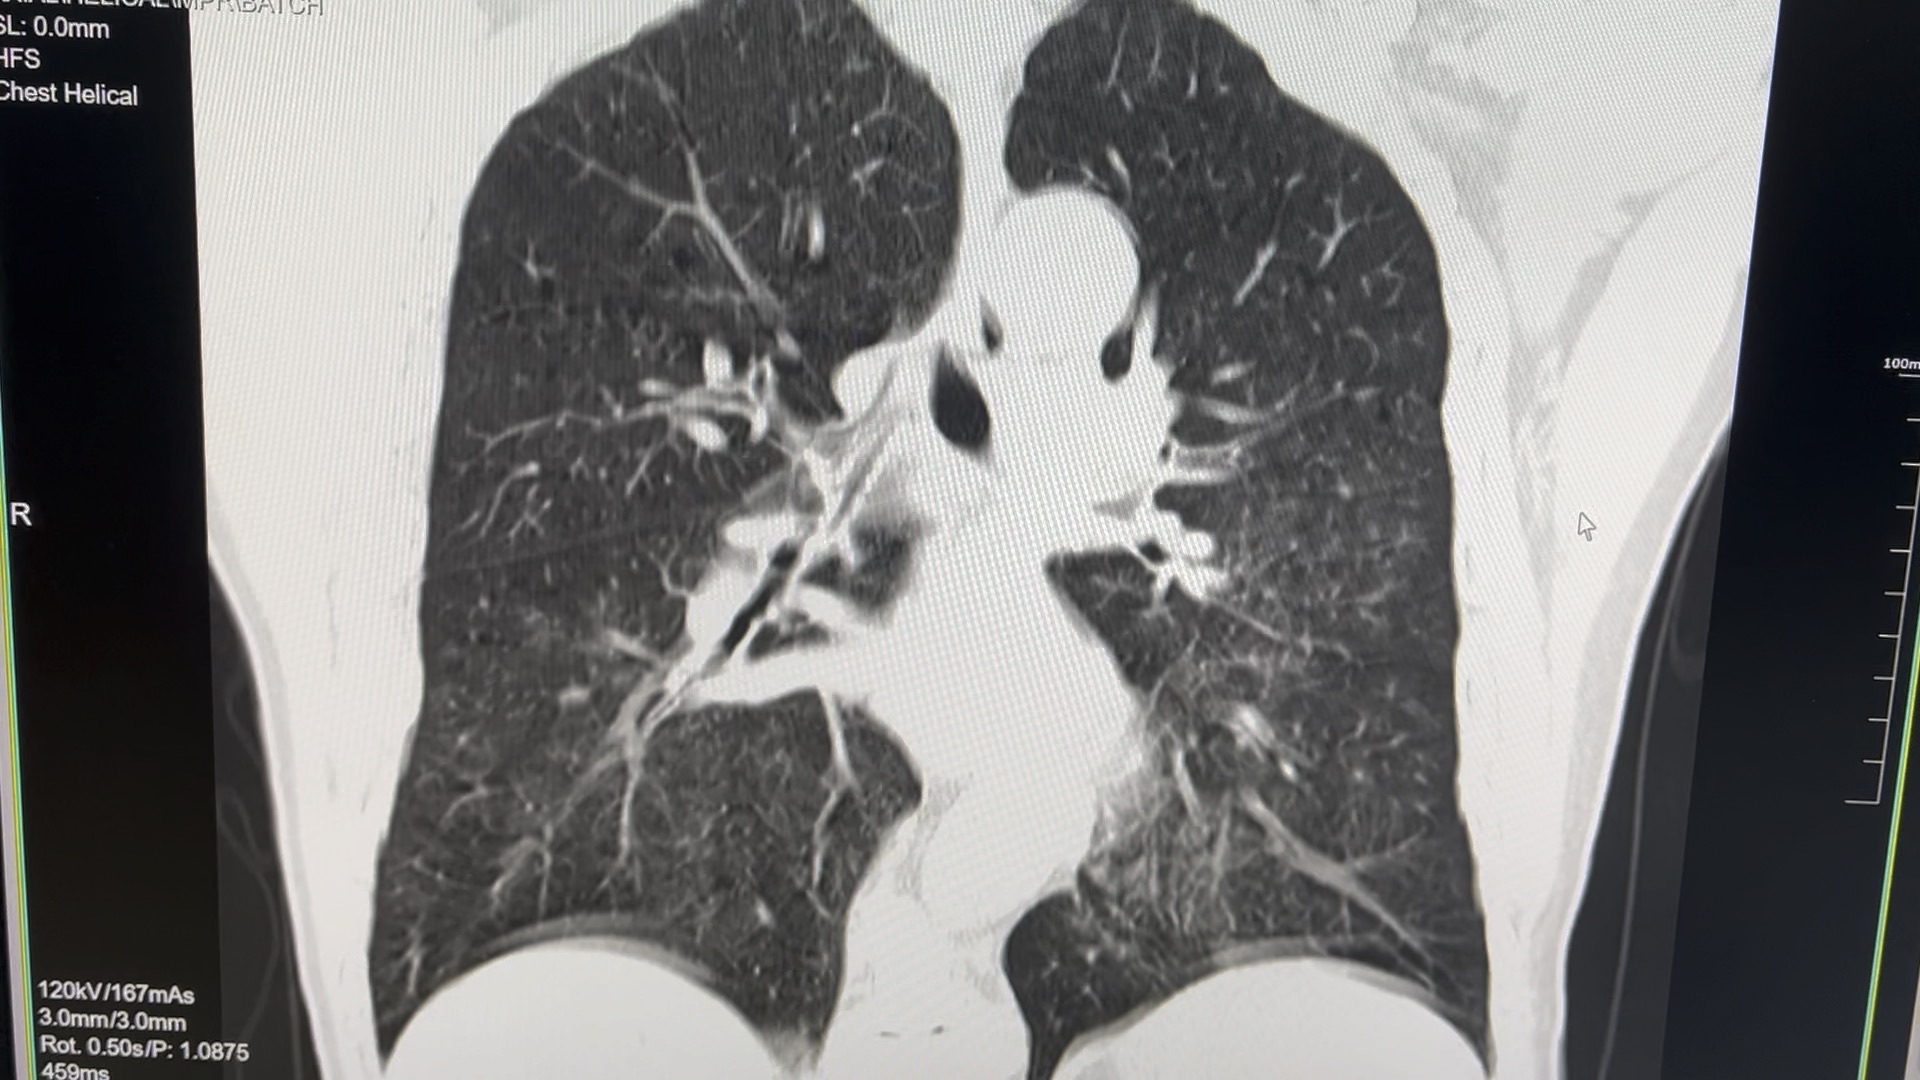

间质性肺水肿待定

图片尺寸1920x1080

m,52,左心衰竭,间质性肺水肿.小叶间隔增厚.

图片尺寸1038x458